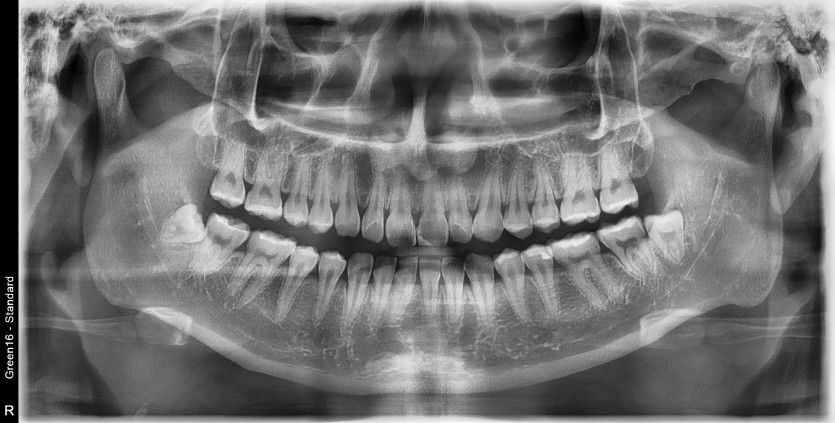

#38,48 사랑니 발치

구강 외과 전문의가 당일 발치했습니다.